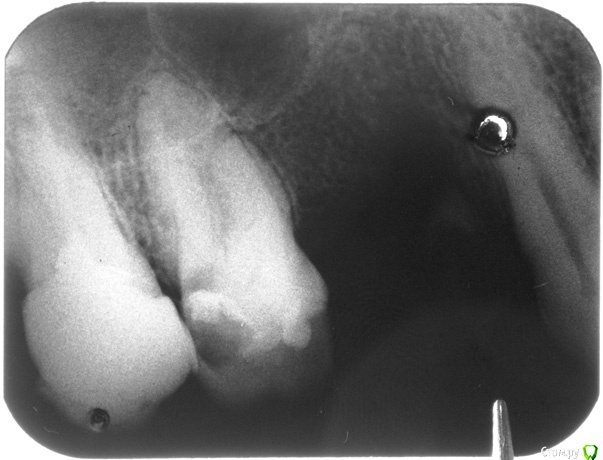

Анбо Опубликовано 13 февраля, 2017 Поделиться Опубликовано 13 февраля, 2017 ЗдравствуйтеПолтора месяца назад сильно заболел зуб – 6 верхн.Потом острая боль прошла, но образовалась небольшая припухлость десны, к которой прикасаться больно. В районной поликлинике врач сказала, что там ничего нет и делать снимок отказалась.Долгое время так маленькая припулость и держалась и особо не мешала.Но вчера раздуло всю щеку.Сделали снимок (наконец) – киста. Теперь она говорит, что только удалять.Может есть еще шансы? Лечат же резекцией. Может еще как? Ссылка на комментарий

Доктор Добрых Дел Опубликовано 13 февраля, 2017 Поделиться Опубликовано 13 февраля, 2017 Я кисты никакой не вижу. 3 Ссылка на комментарий

Анбо Опубликовано 13 февраля, 2017 Автор Поделиться Опубликовано 13 февраля, 2017 Хм... А что видите и что тогда посоветуете?Может я просто перефоткал плохо?Мне она сказала, что в корне кариозная полость, и от нее - киста... Ссылка на комментарий

red_butler Опубликовано 13 февраля, 2017 Поделиться Опубликовано 13 февраля, 2017 Хм... А что видите и что тогда посоветуете? Rg является дополнительным способом диагностики. Если дистанцироваться от Ваших жалоб, то на снимке осложненный кариес, а именно хронический апикальный периодонтит. Диагноз киста можно поставить проведя гистологическое исследование. И если мне не мерещится, то в области первого премоляра есть фрагмент корня.Шестой зуб, если степень его разрушения позволяет провести реставрацию, нужно лечить у эндодонтиста. 1 Ссылка на комментарий

Анбо Опубликовано 15 февраля, 2017 Автор Поделиться Опубликовано 15 февраля, 2017 (изменено) ОПТГ нет. Сходил к другому врачу. Сказала, что снимок плохой (темный), но тоже увидела кариес корня и кисту. Вряд ли они сговорились. Но они зато видели снимок «живьем». Может плохой снимок + потеря качества при перефотографировании привели к тому, что на приведенном здесь фото что-то теряется? Вот поиграл светом-тенью – может что-то проявилось? Это не то, что стрелочками обозначил? Но она была не столь категорична по поводу удаления («Лучше удалить, но можно пока оставить. Но все равно через некоторое время все вернется»). И сказала, что если зуб вскрывать, то будет еще хуже. Мне сделали разрез, чтобы выпустить гной, и назначили азитромицин. Прокомментируйте, пожалуйста.Если на снимке не все видно, укажите, пожалуйста, какие части наиболее важны, я могу в фотошопе сделать их наиболее контрастными. Гистологическое исследование, о котором писал red_butler, не везде делают? Оно имеет какое-нибудь более конкретное название? Изменено 15 февраля, 2017 пользователем Анбо Ссылка на комментарий

Гарриевич Опубликовано 15 февраля, 2017 Поделиться Опубликовано 15 февраля, 2017 это дно верхнечелюстной пазухи"кисты" не видать 5 Ссылка на комментарий

DmitrySH Опубликовано 16 февраля, 2017 Поделиться Опубликовано 16 февраля, 2017 Если у Вас еще сохранились сомнения, то сделайте КТ , все будет понятно. Никакой кисты, просто бухта гайморовой пазухи. 1 Ссылка на комментарий

Bier Опубликовано 16 февраля, 2017 Поделиться Опубликовано 16 февраля, 2017 там четко есть гранулема на медиальном корне. Может ее и назвали "кистой"?? 2 Ссылка на комментарий